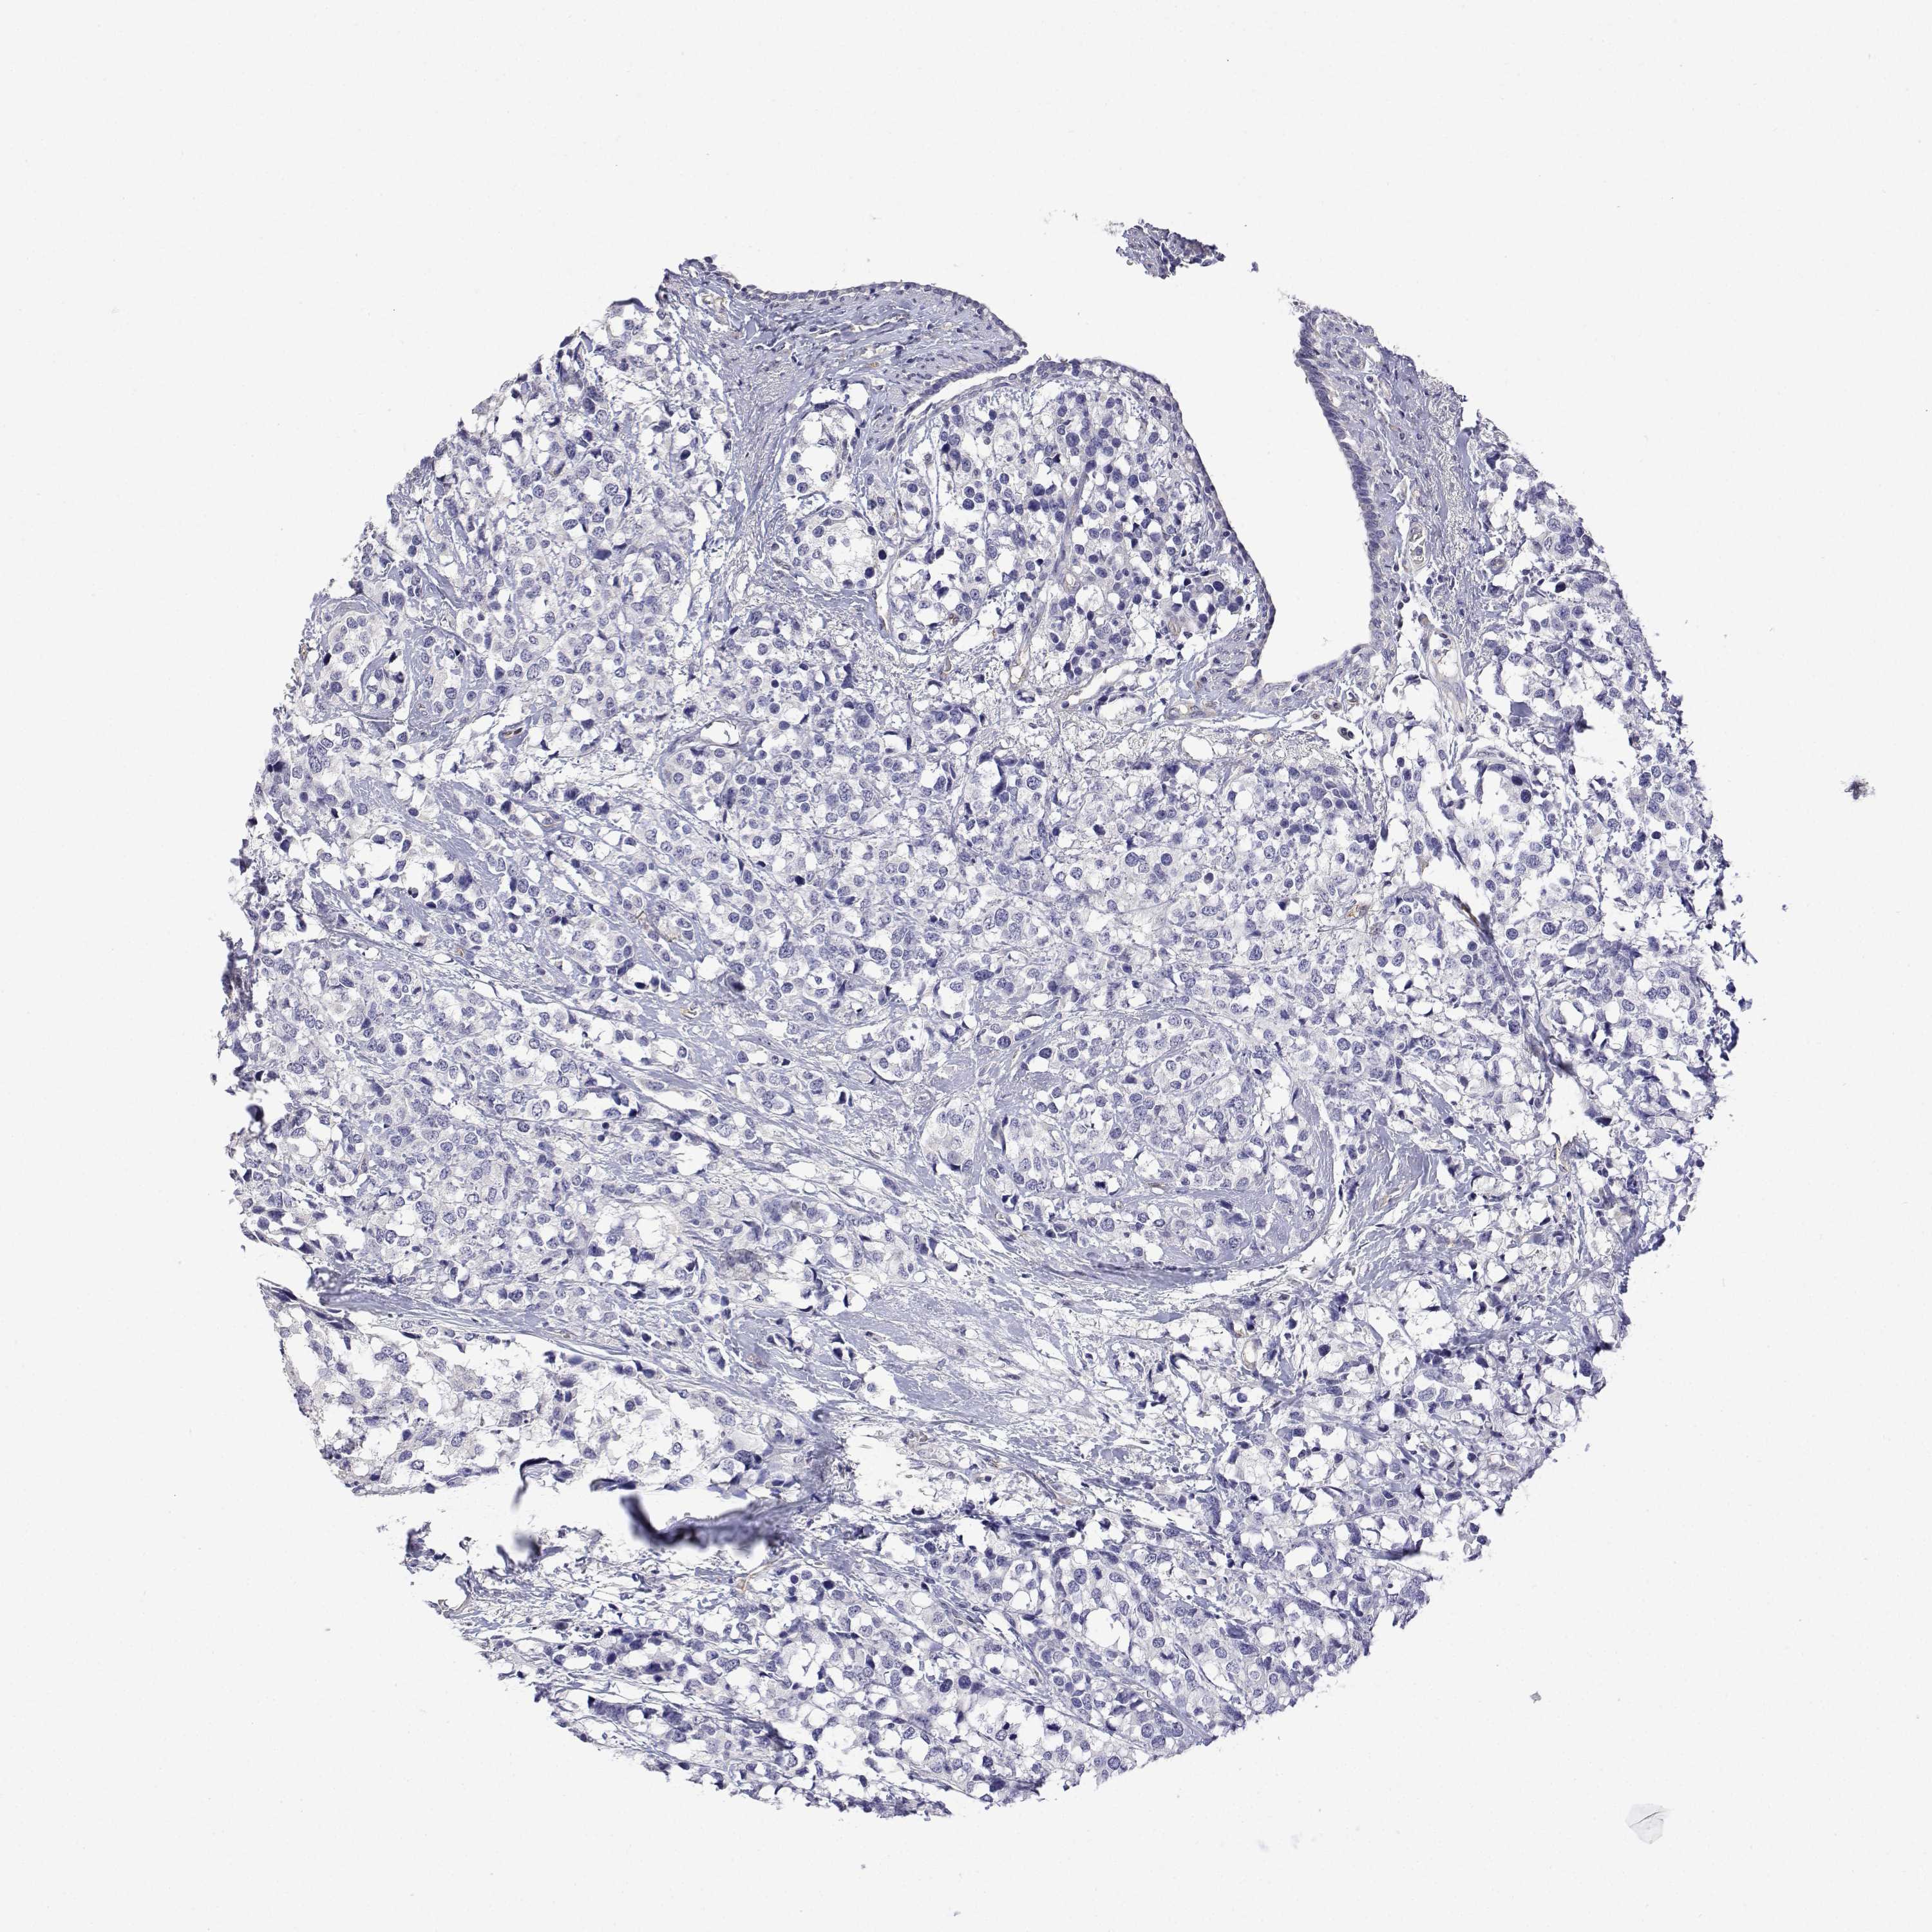

CANCER BREAST CANCER Show tissue menu

BRCA TCGA BRCA VALIDATION PROTEIN EXPRESSION

Breast cancer

Human cancer